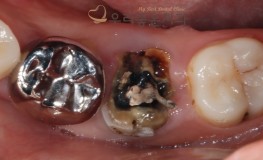

충치치료

우리좋은치과 Crack으로 인한 치아 발치 및 임플란트 식립 (주** 21.03...